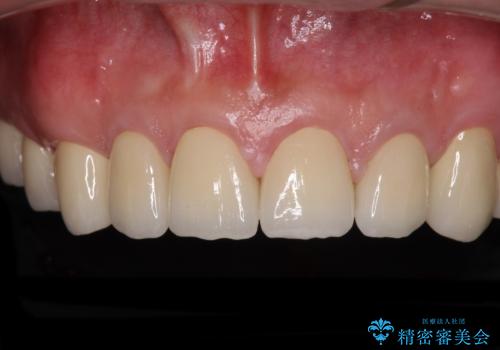

当初は前歯6歯をオールセラミッククラウンで補綴する予定でしたが、前歯が綺麗に仕上がったことで、奥歯まで延長して補綴することとしました。

黄ばんだ前歯や白すぎたクラウン、プラスチックの継ぎ接ぎなどを全てオールセラミッククラウンの統一感のある前歯に仕上げました。